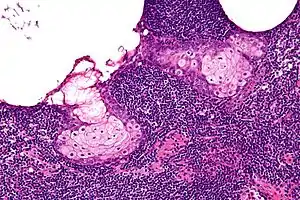

High magnification micrograph of a sebaceous lymphadenoma. H&E stain.